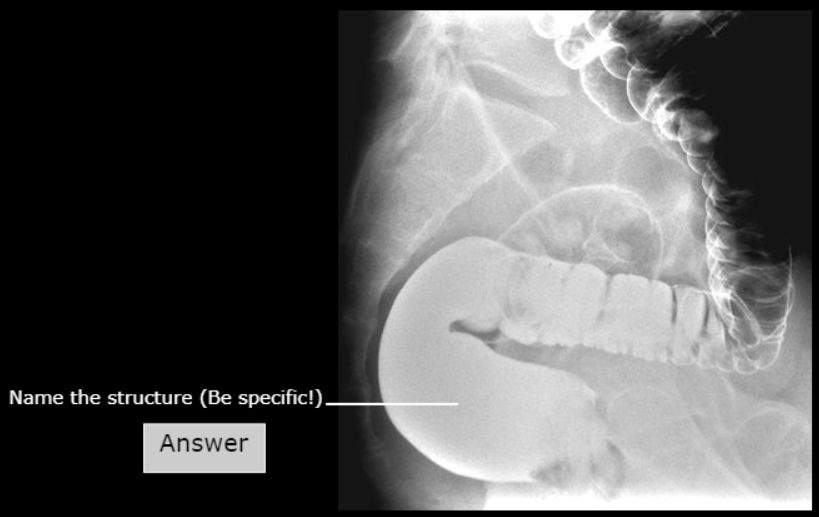

Ampulla of the Rectum